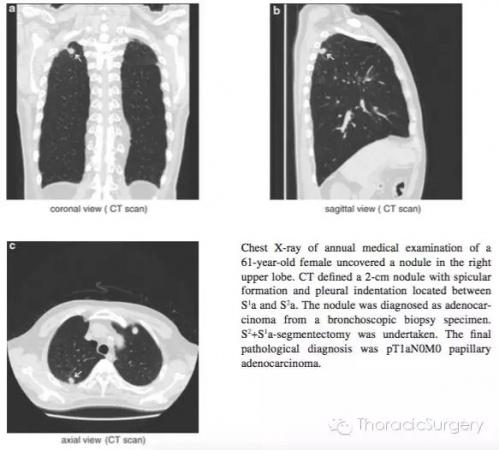

患者,男性,58岁,常规胸片发现右上肺结节。CT可见一S3b的1cm结节,周围伴有毛刺。CT定位下活检病理证实为肺腺癌。予以S3肺段切除。最终的病理学诊断为pT1aN0M0**状腺癌。

图.3.3.1 通过HRCT影像从轴状面,冠状面和矢状面明确肺段动脉,静脉和支气管。气管插管后通过支气管镜进一步明确B1,B2和B3分支形状和尺寸。本书中的图片是段支气管和动脉最常见的分支类型,即右上支气管分为B1和B2和B3;A1和A3段间动脉分支源于肺动脉上干。A2a是源于肺动脉上干的反支,A2b为A2的升支;段间静脉源于尖段和中央静脉。第三肋间推荐作为S2段切除的主操作孔。